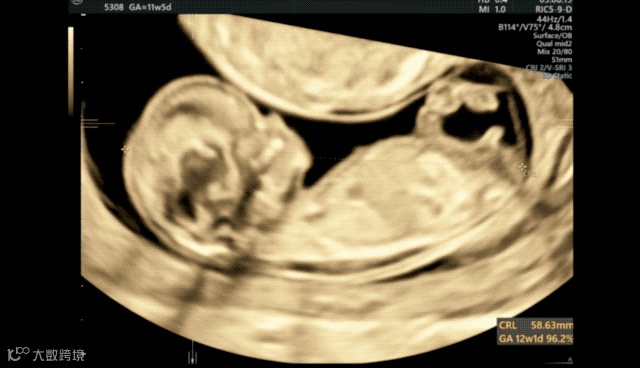

微调后,我们在菜单内选择a平面-单幅图像,放大,就可以测量头臀长。

接着继续放大a平面,使胎儿头胸部占据整个画面,微调后显示NT的两条线,降低增益,完成NT测量就可以了。